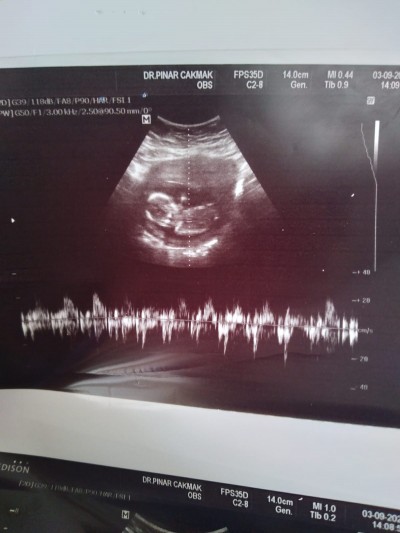

Sizce nedir cinsiyeti

image